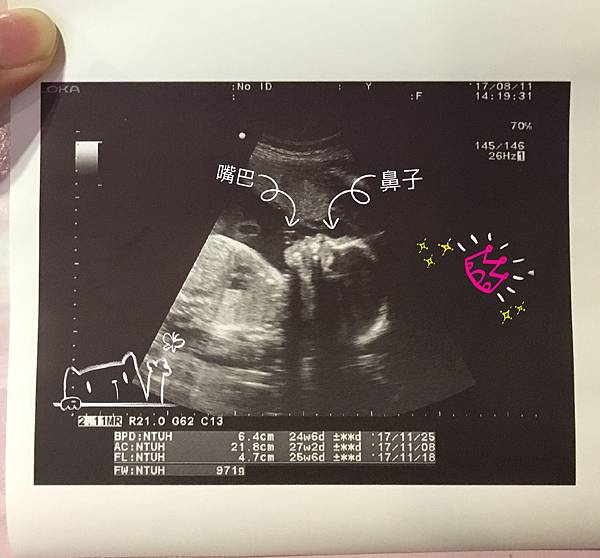

董醫師照超音波非常細心,會告訴你這是哪裡哪裡

還有數手指頭,反而是我常常聽到放空(這位媽媽這樣對嗎)

23週自費高層次超音波

很多人高層次會選擇去台安等大醫院,但我還是在許世賓這裡照啦

雖然排不到董醫師了,但幫我們照的醫師也很專業很仔細

這天就確定肚皮裡的是女孩了![]()

寶貝超喜歡把手手放在臉上